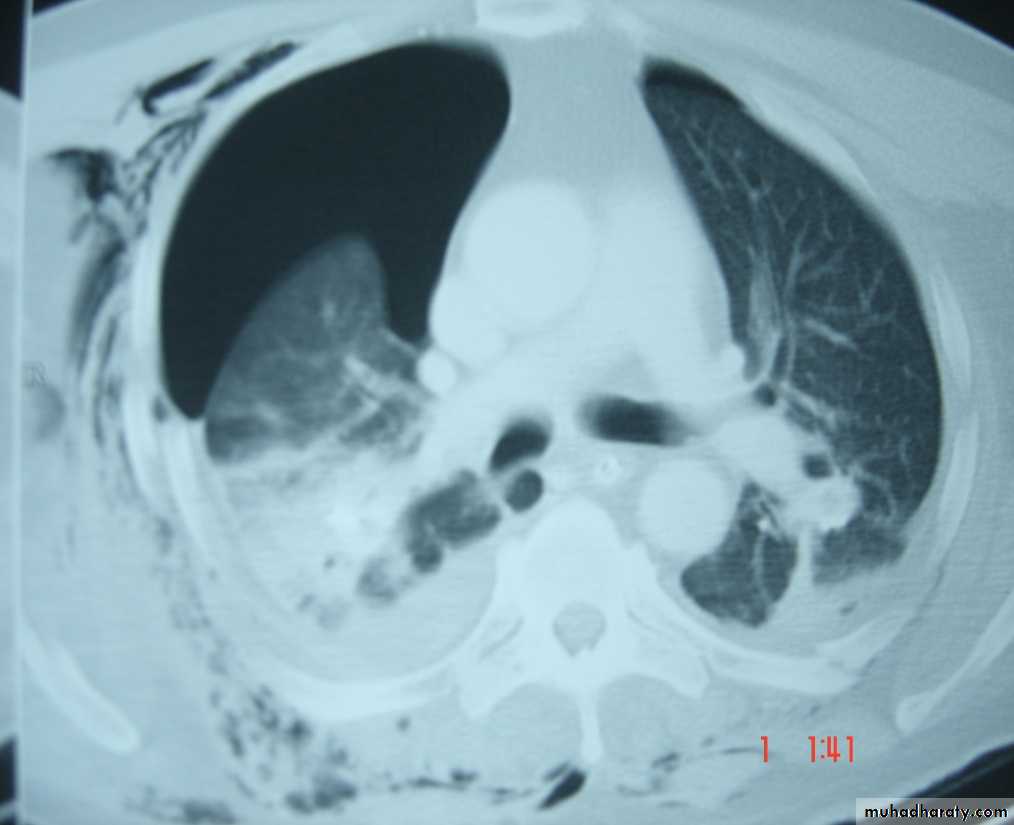

• Chest X-ray ,CT chest ..

• Pathology :-A-Central type is the commonest (75%).It arises in one of the main bronchi or their primary division leading to bronchial obstruction with secondary changes in the lung such as atelectasis .B-Peripheral type (25%) arises from the smaller bronchi and remains symptom less for long time .

Histologically Squamous cell Ca (SCC) 60% , smoker , centrally located ,metastasizes to mediastinal & supraclavicular LN . Adenocarcinoma (15% ) , located peripherally , more in women .Tends to metastasizes to the liver , brain ,bone & adrenals in addition to the LN Undifferentiated carcinoma (oat) cell carcinoma and large cell carcino(20-30%) which includes small ma Alveolar cell carcinoma , located peripherally ,metastasizes to the liver and adrenalsRecent classification..Non small & small cell carcinoma

• Differential diagnosis of a solitary lung lesion (COIN LESION)

• 1-Hydatid cyst 4- Primary benign lesion• 2-Tuberculoma 5-primary malignancy of the lung

• 3-Angiomatous malformation (AV fistula) 6-metastatic tumors